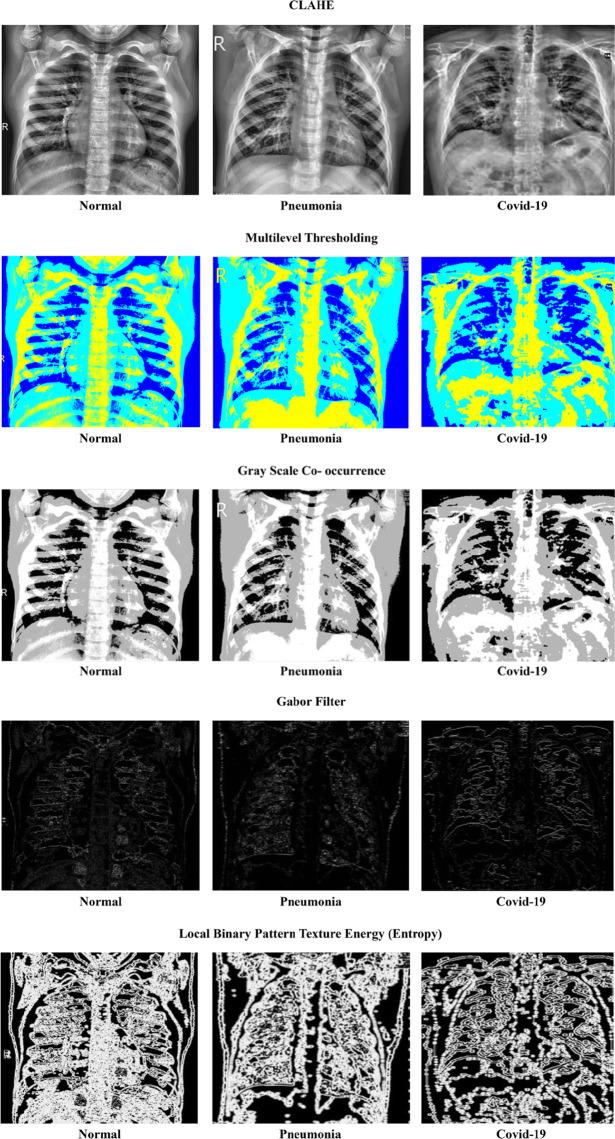

There is a broad range of novel Coronaviruses (CoV) such as the common cold, cough, and severe lung infections. The mutation of this virus, which originally started as COVID-19 in Wuhan, China, has continued the rapid spread globally. As the mutated form of this virus spreads across the world, testing and screening procedures of patients have become tedious for healthcare departments in largely populated countries such as India. To diagnose COVID-19 pneumonia by radiological methods, high-resolution computed tomography (CT) of the chest has been considered the most precise method of examination. The use of modern artificial intelligence (AI) techniques on chest high-resolution computed tomography (HRCT) images can help to detect the disease, especially in remote areas with a lack of specialized physicians. This article presents a novel metaheuristic algorithm for automatic COVID-19 detection using a least square support vector machine (LSSVM) classifier for three classes namely normal, COVID, and pneumonia. The proposed model results in a classification accuracy of 87.2% and an F1-score of 86.3% for multiclass classifications from simulations. The analysis of information transfer rate (ITR) revealed that the modified quantum-based marine predators algorithm (Mq-MPA) feature selection algorithm reduces the classification time of LSSVM by 23% when compared to the deep learning models.

存在多种新型冠状病毒(CoV),可引发普通感冒、咳嗽和严重肺部感染等病症。这种最初在中国武汉以新冠病毒病(COVID-19)形式出现的病毒发生了变异,并在全球持续迅速传播。随着这种变异病毒在全球传播,对于印度等人口大国的医疗部门而言,患者的检测和筛查程序变得繁琐。通过放射学方法诊断新冠病毒病肺炎时,胸部高分辨率计算机断层扫描(CT)被认为是最精确的检查方法。在胸部高分辨率计算机断层扫描(HRCT)图像上使用现代人工智能(AI)技术有助于检测该疾病,特别是在缺乏专业医生的偏远地区。本文提出了一种新颖的元启发式算法,用于使用最小二乘支持向量机(LSSVM)分类器对正常、新冠和肺炎三类进行自动新冠病毒病检测。从模拟结果来看,所提出的模型在多类分类中的分类准确率为87.2%,F1分数为86.3%。信息传输率(ITR)分析表明,与深度学习模型相比,改进的基于量子的海洋捕食者算法(Mq-MPA)特征选择算法可将LSSVM的分类时间减少23%。